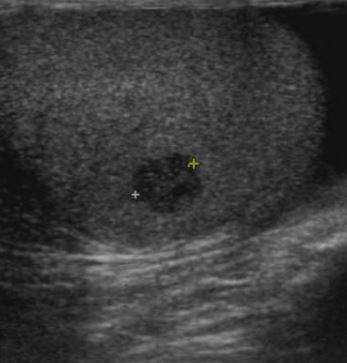

Il sospetto clinico viene confermato dall’ecografia scrotale che determina la sede, le dimensioni e la vascolarizzazione della lesione.